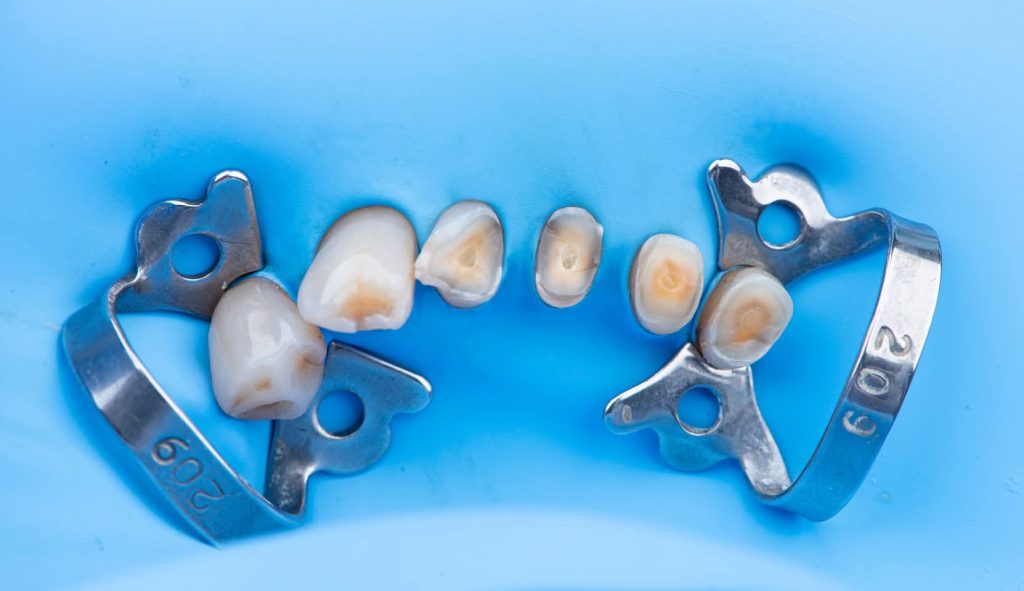

Preparation of teeth and insertion of the fixed prosthesis.

The lower arch was managed similarly to the upper arch.